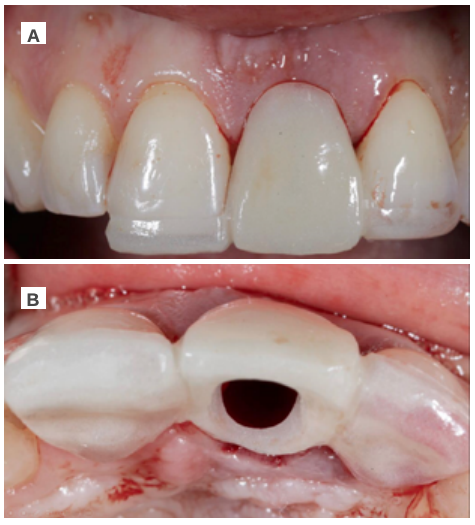

Clinical case: A 32-year-old female patient who attended for a possible root fracture of the upper left central incisor (ULCI), accompanied by a periodontal abscess at the bottom of the vestibule of the same tooth. A clinical and radiological examination established that the prognosis of the ULCI was unfavourable for conservative treatment. After evaluating the clinical features of the case, the treatment plan to extract the ULCI followed immediately by an osseointegrated implant (OII) and loading of a provisional prosthesis on the implant.

Conclusions: Rehabilitation on implants in situations of tooth loss in the aesthetic anterior sector, especially in young patients, requires a multidisciplinary treatment plan to extract the tooth and insert an OII in the correct 3-dimensional position. Various aspects need to be taken into account for this, particularly the residual remaining bone, the position of the gingival margin and preservation and conditioning of the peri-implant hard and soft tissues by means of grafts and proper handling of provisional prosthesis, until an ideal emergence profile and gingival contour is achieved before the final crown.

The benefits of immediate loading include a marked reduction in surgical interventions, less temporary dilation of the treatment and even better psychological and social wellbeing for the patient. In cases with a significant aesthetic requirement, immediate loading or provisionalisation, and post-extraction placement of the OII minimise alterations due to tooth loss and maintain the emergence profile, soft tissue contour and gingival papillae5-7.

Different protocols have also been established for the management of the anterosuperior aesthetic sector, in addition to performing the immediate implant and provisional crown, including placing material between the OII and the buccal cortical to minimise possible collapse and the management of peri-implant soft tissue8-11.